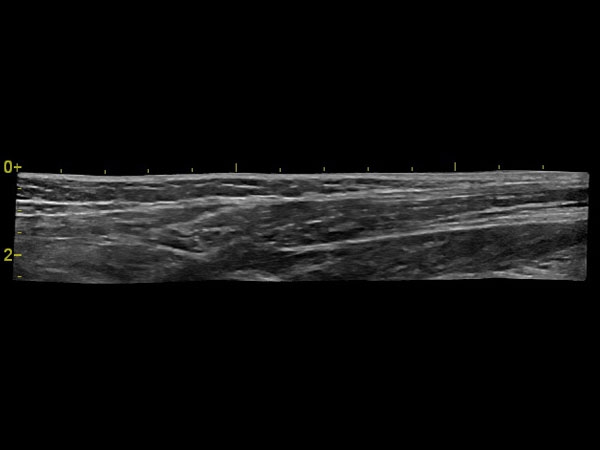

Панорамное сканирование:

Да

IMT (Intima Media thickness):